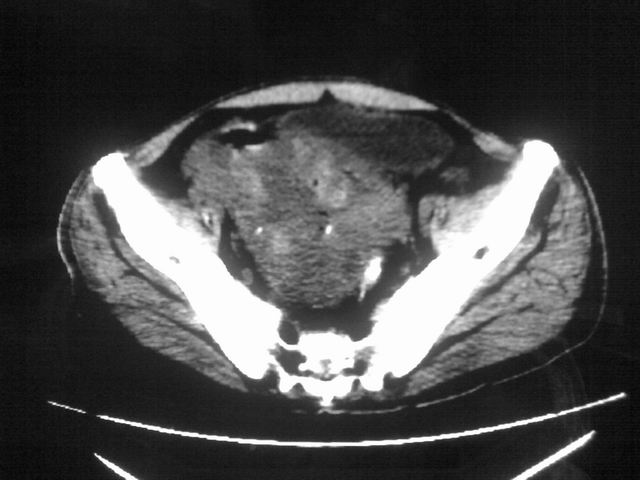

患者m 56岁,盆腔及下腹部胀痛半年,加重1月余,消瘦\中重度贫血.(附:平扫时直肠的高信号为,残留的钡剂).补一下病史:胃镜及纤维结肠镜均无明显异常.

膀胱后方及直肠前方见巨大混杂密度影,与前列腺相连且向膀胱内突入,精囊腺显示不清;考虑前列腺癌侵犯精囊、膀胱。

膀胱及直肠间有不规侧的软组织密度影,内密度不均匀。其内有坏死囊变,前列腺及精囊腺,膀胱后壁受浸。结合病史考虑腹膜后肉瘤可能性大。